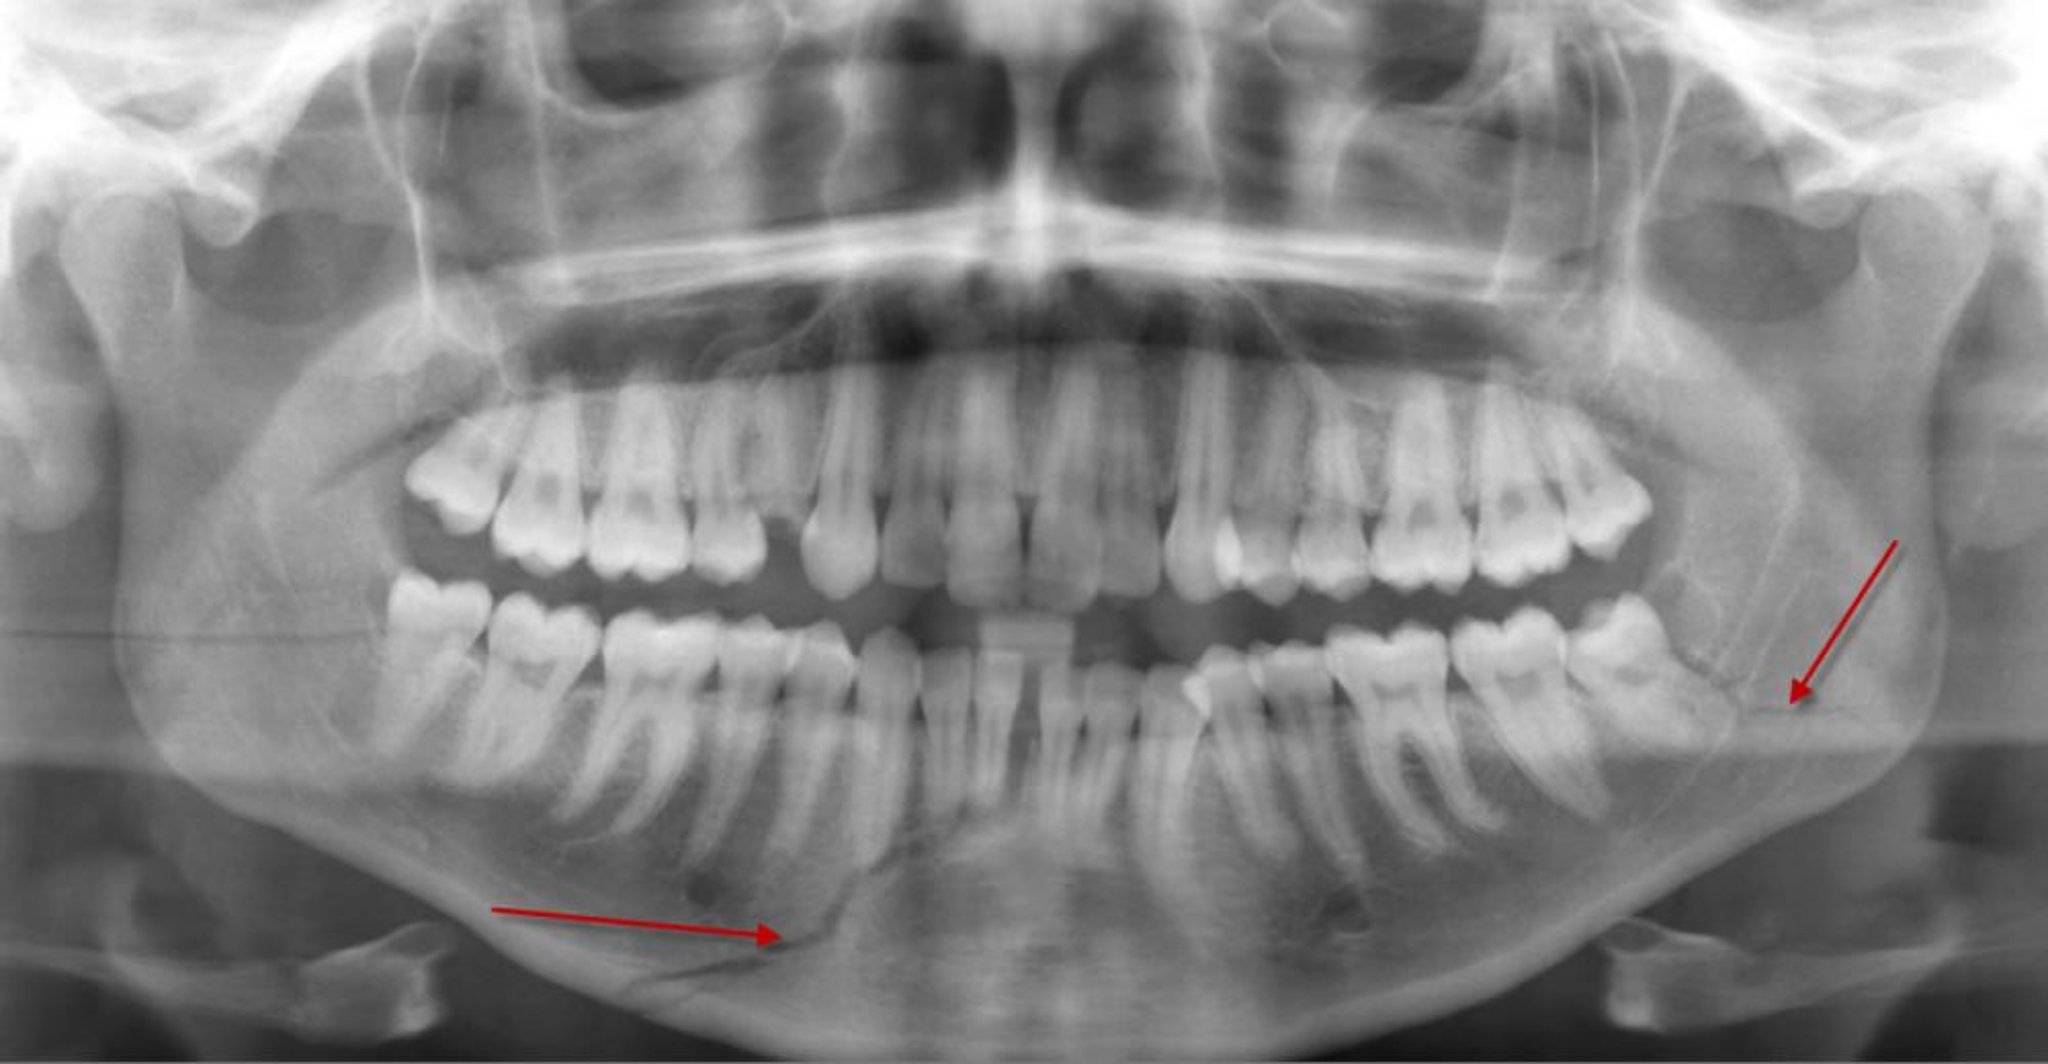

Перелом тела нижней челюсти

Эта панорамная рентгенограмма показывает просветление (стрелка внизу) в теле нижней челюсти, представляющее собой перелом, который достигает корней некоторых передних нижних зубов. Также имеется перелом левого мандибулярного угла (стрелка).